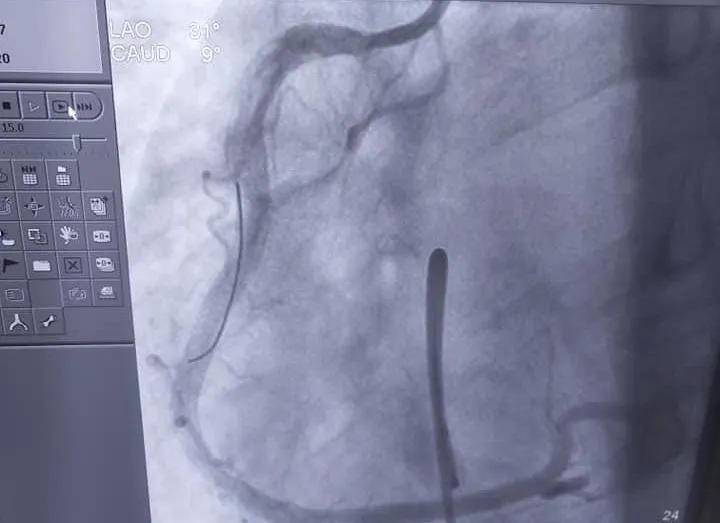

Tại phòng can thiệp, các bác sĩ đã tiến hành chụp mạch vành, kết quả tắc động mạch vành phải kèm nhiều huyết khối, phải tiến hành hút huyết khối, đặt Stent vào động mạch vành phải, khai thông nhánh động mạch này. Sau can thiệp, bệnh nhân ổn định trở lại, tỉnh táo, giảm đau ngực, giảm khó thở và ra viện sau 1 tuần.